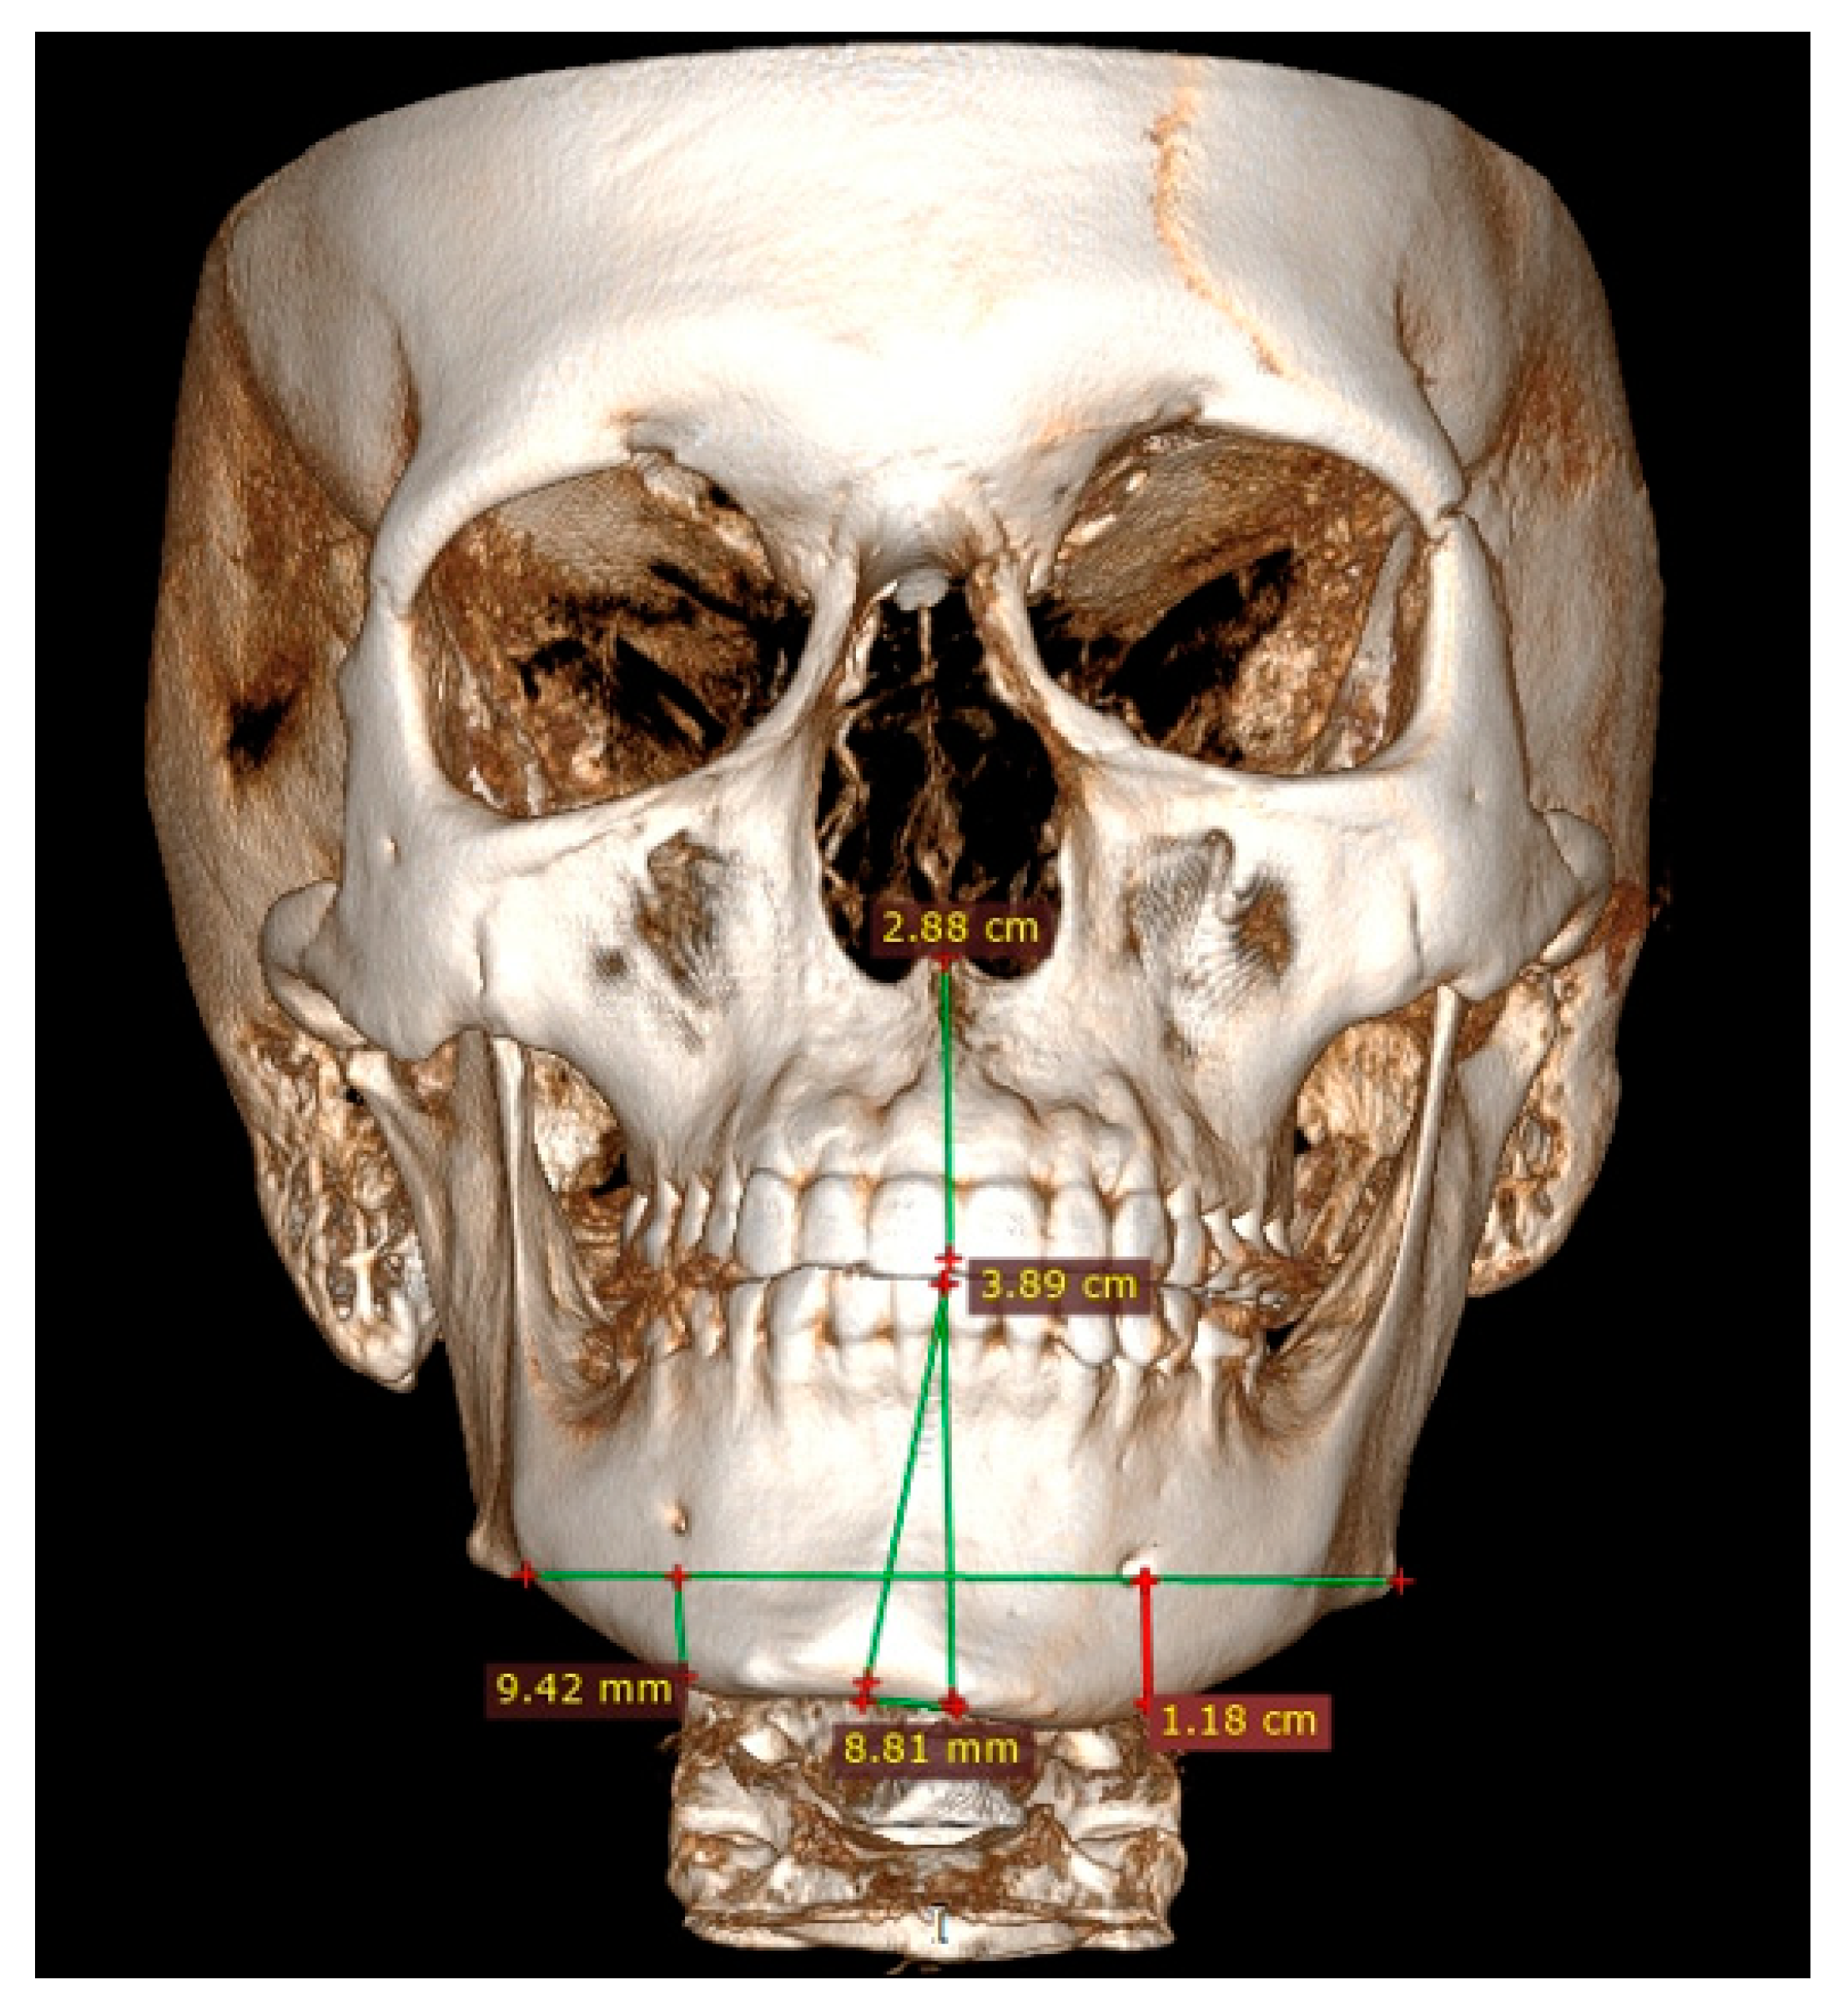

3.4. Low-Dose Computer Tomography

Both panoramic radiographs and LDCT evaluations are important for any surgery planning. There is a possibility to estimate the shape and position of the mandibular canal while tracing its course on 3D evaluation and then estimating the degree of surgery in MIB (Figure 3 and Figure 4). Secondly, based on the studied patients’ data, the authors also include that the position of the mental foramina, chin deviation, and Go reference points described herein are valuable reference points for future surgical planning. Another important feature possible to estimate on 3D-LDCT is the scope of mandibular basis overgrowth in three dimensions.

Figure 3.

LDCT—evaluation in low-dose CT focused on central symmetry line and differences in measurements between mental foramina, MIB, chin position, and mandibular angle contour.

3.7. 2D versus 3D Surgical Planning

The usage of a 2D-panoramic radiograph is helpful. More important measurements nowadays are made on 3D-virtual planning models (Figure 5). 3D planning might improve surgeons’ insight and the scope of bone evaluation. Because of great improvements in surgical planning, not only 3D-CT/LDCT evaluation is helpful. The usage of 3D stereolithographic models is an alternative method, where surgical cuts and plate bending might be quite easily made before surgery to ensure that the selected surgical approach is the most adequate of all. In cases of asymmetry visualized in patients in face view after orthognathic, surgical, and orthodontic treatment, some detailed total mandibular symmetry correction protocols are needed. Direct 3D-LDCT planning based on the used anatomical reference points presented herein is helpful in restoring facial balance and mandibular symmetry (Figure 6 and Figure 7). The authors’ future studies will focus on the 3D evaluation of facial skeleton, soft tissue changes in CT/MR, and lateral profile alterations; because of that, any other data are excluded from this study.

Figure 5.

Patient CT evaluation after BSSO. Presented frontal scan underlines still present asymmetry in the left mandibular basis, which was not fully camouflaged after BSSO and required further surgical approaches for definitive mandibular symmetry correction.